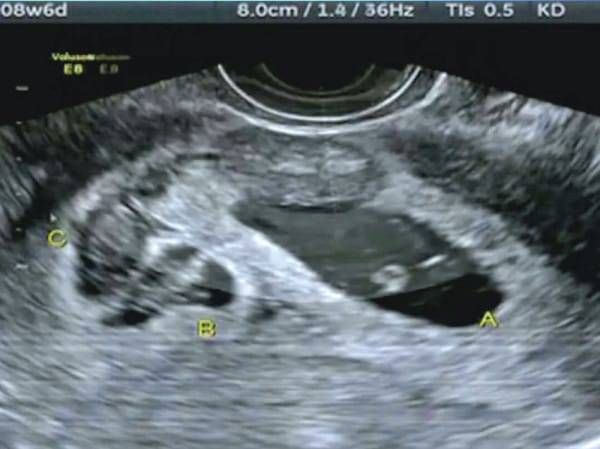

30 nov. 2017, 16:10ActualÎnsărcinată cu o fetiță, a mers la ecograf. Verdict șoc: ce apăruse în burtă, lângă copil